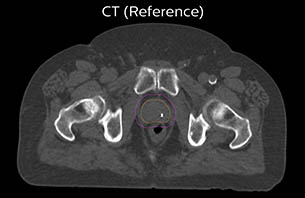

MR-only based planning for prostate cancer radiation therapy treatment

A 77-year-old male with prostate cancer cT3aN0M0, Gleason 8 and PSA 52 μg/L referred to androgen deprivation and radiation therapy with a prescribed dose of 50 Gy to the pelvic lymph node regions and 76 Gy to the prostate.

Turku CT reference case 5

The 3D T1W FFE mDIXON sequence provides in-phase, water and fat images in one acquisition. Target and organs-at-risk are delineated on the 3D T2W TSE images. Prostate GTV is shown in orange, PTV in purple. The 3D bFFE sequence is used by the planner to mark the position of the fiducial markers (gold anchors) and contours are transferred to the digitally reconstructed radiographs (DRRs).

Based on the 3D T1W mDIXON images, MR-based density maps (MRCAT) are automatically generated. The VMAT (Volumetric Modulated Arc Therapy) plan is generated in TPS, based on MRCAT as primary image set. During the commissioning phase, dosimetric agreement between MRCAT-based and CT-based dose plans was studied and differences in the PTV dose were found to be minimal (<1% for most patients). Average difference in PTV mean values was 0.8% over the study group (n=62).